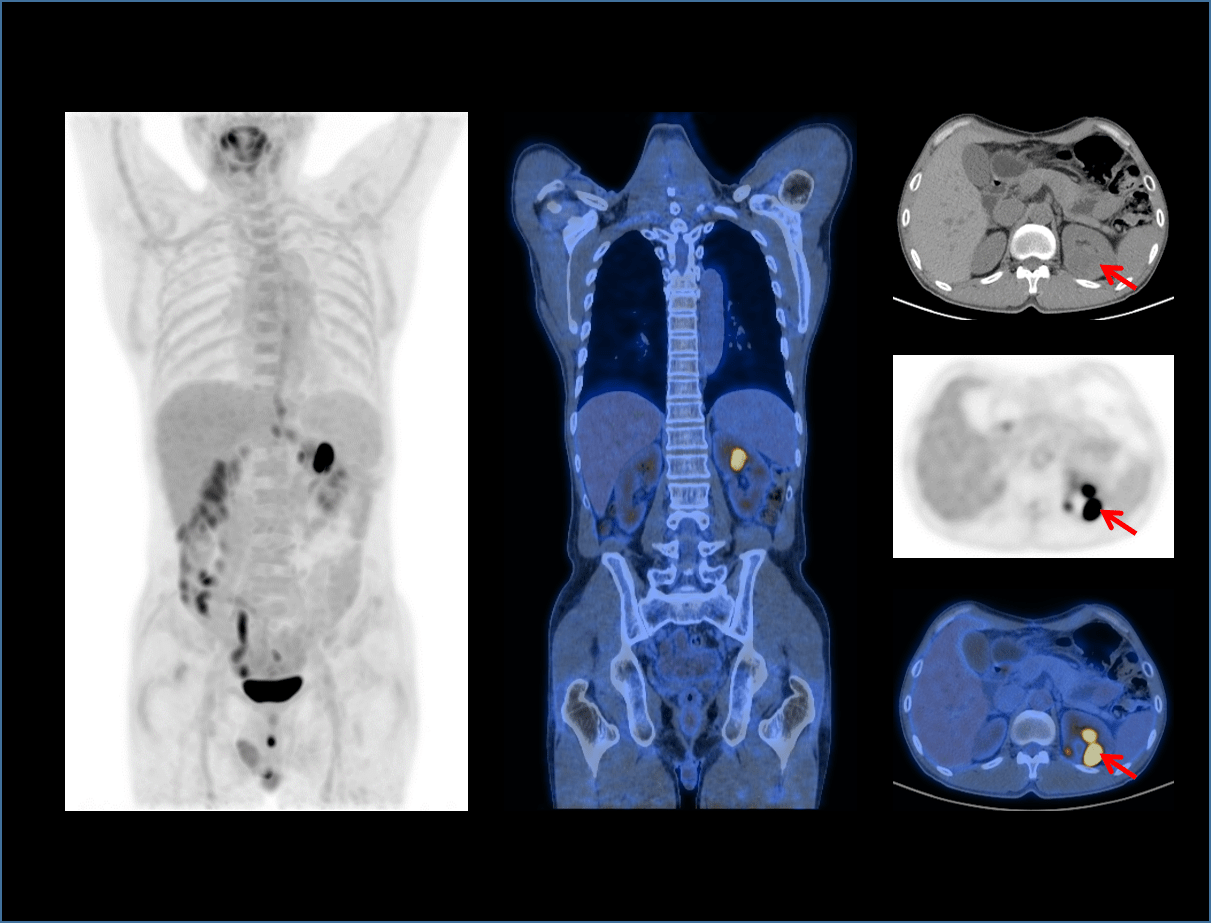

With the unique Integrated-Light-Guide Digital PET technology and a 160-slice CT system, uMI Vista combines high quality functional images with fine anatomical structure visualization. The state-of-the-art reconstruction technology and comprehensive applications further boost diagnostic precision in oncology, neurology and cardiology.

24cm Large Axial FOV

4 beds positions for a whole-body scan

Expand clinical efficiency.

High speed scanning

Increase patient throughput.